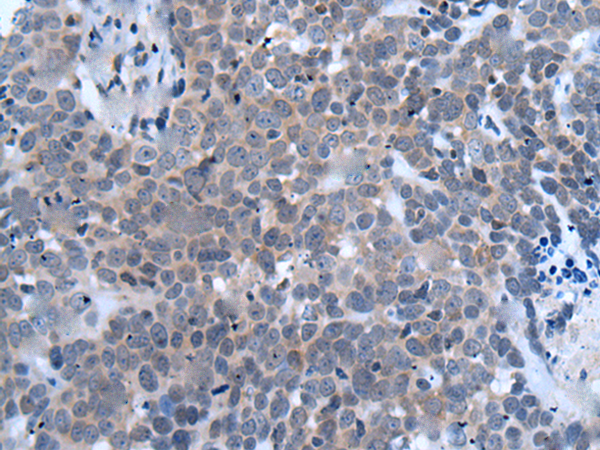

IHC positive control: |

Human thyroid cancer |

IHC Recommend dilution: |

10-50 |